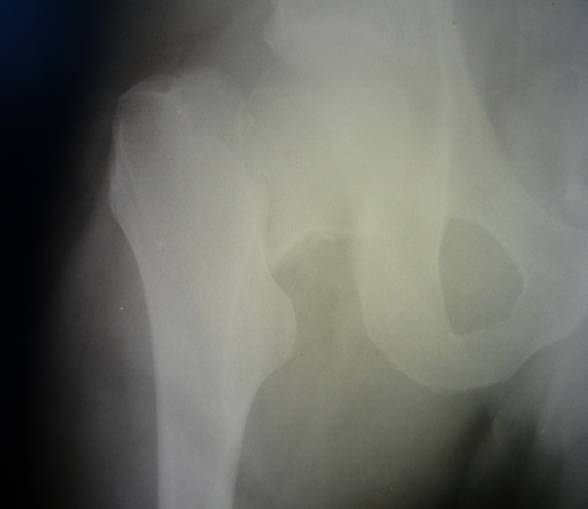

Рентгенологическое исследование правого тазобедреннго сустава от 6.03:

суставные поверхности четкие, определяется свободный варусный перелом шейки правого бедра с ротацией дистального отломка кнаружи. Верхушка большого вертела чуть приподнята, малый вертел увеличен за счет поворота дистального отломка, уменьшено расстояние между ним и головкой белренной кости, тени межвертельного гребня и шейки накладываются, шеечно- диафизарный угол уменьшен, длина шейки уменьшена.